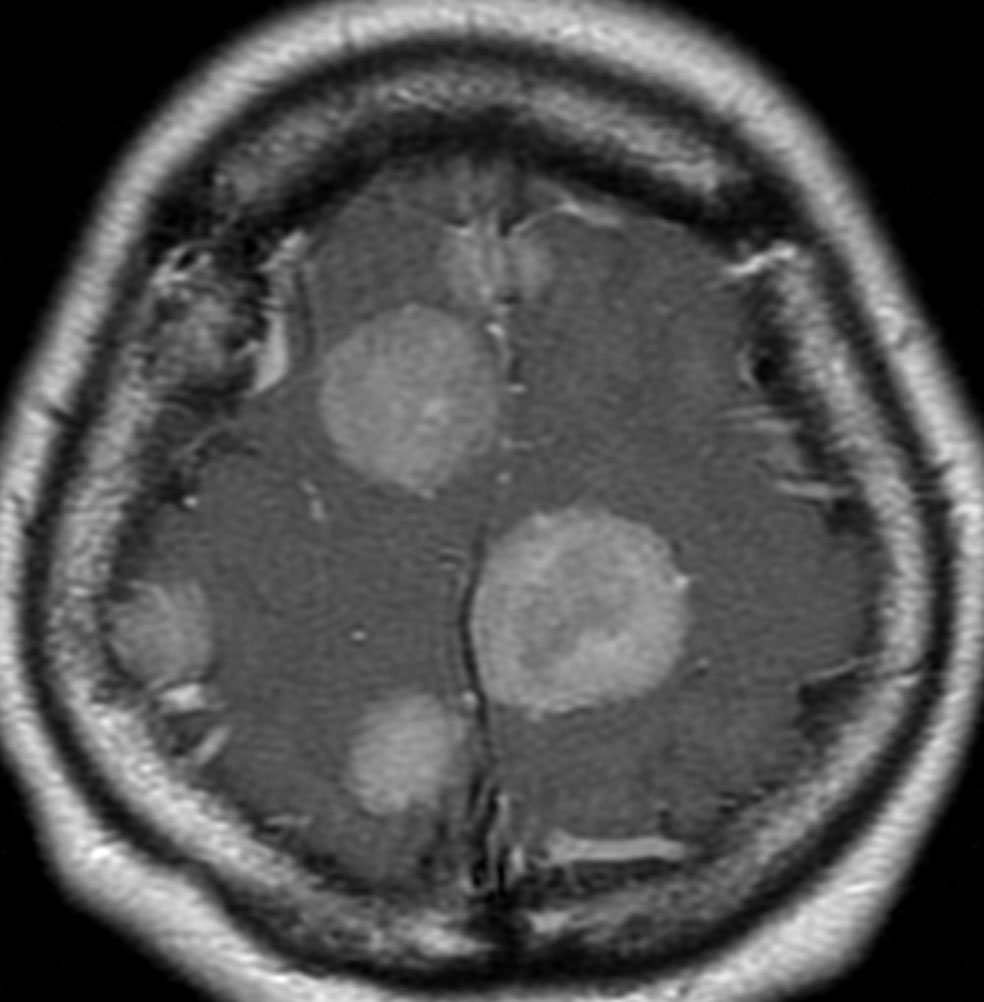

片側髄膜腫症 unilateral meningiomatosis

50歳ころから15年間に3回の開頭手術を受けている患者さんです。parasagittal, falx, convexityなど6個の髄膜腫がすでに摘出されています。左側だけ,テント上だけに髄膜腫が20個くらい多発していました。これらはグレード1で,anaplastic meningiomaの転移ではありません。

やがて蝶形骨縁の髄膜腫の増大速度が早まりatypical meningiomaとなりました。MIB-1 index が10%の高値でした。病理学的にも,psamomatous meningiomaなど様々な種類の髄膜腫が多発しています。

初発時から多発性髄膜腫であり,最初の手術で左側テント上の硬膜を広範囲に摘出しておくべきでした。このような病態は若年者でもみられることがあり,胎生期の硬膜の原基になる細胞にmutationが生じたとしか考えづらいものです。